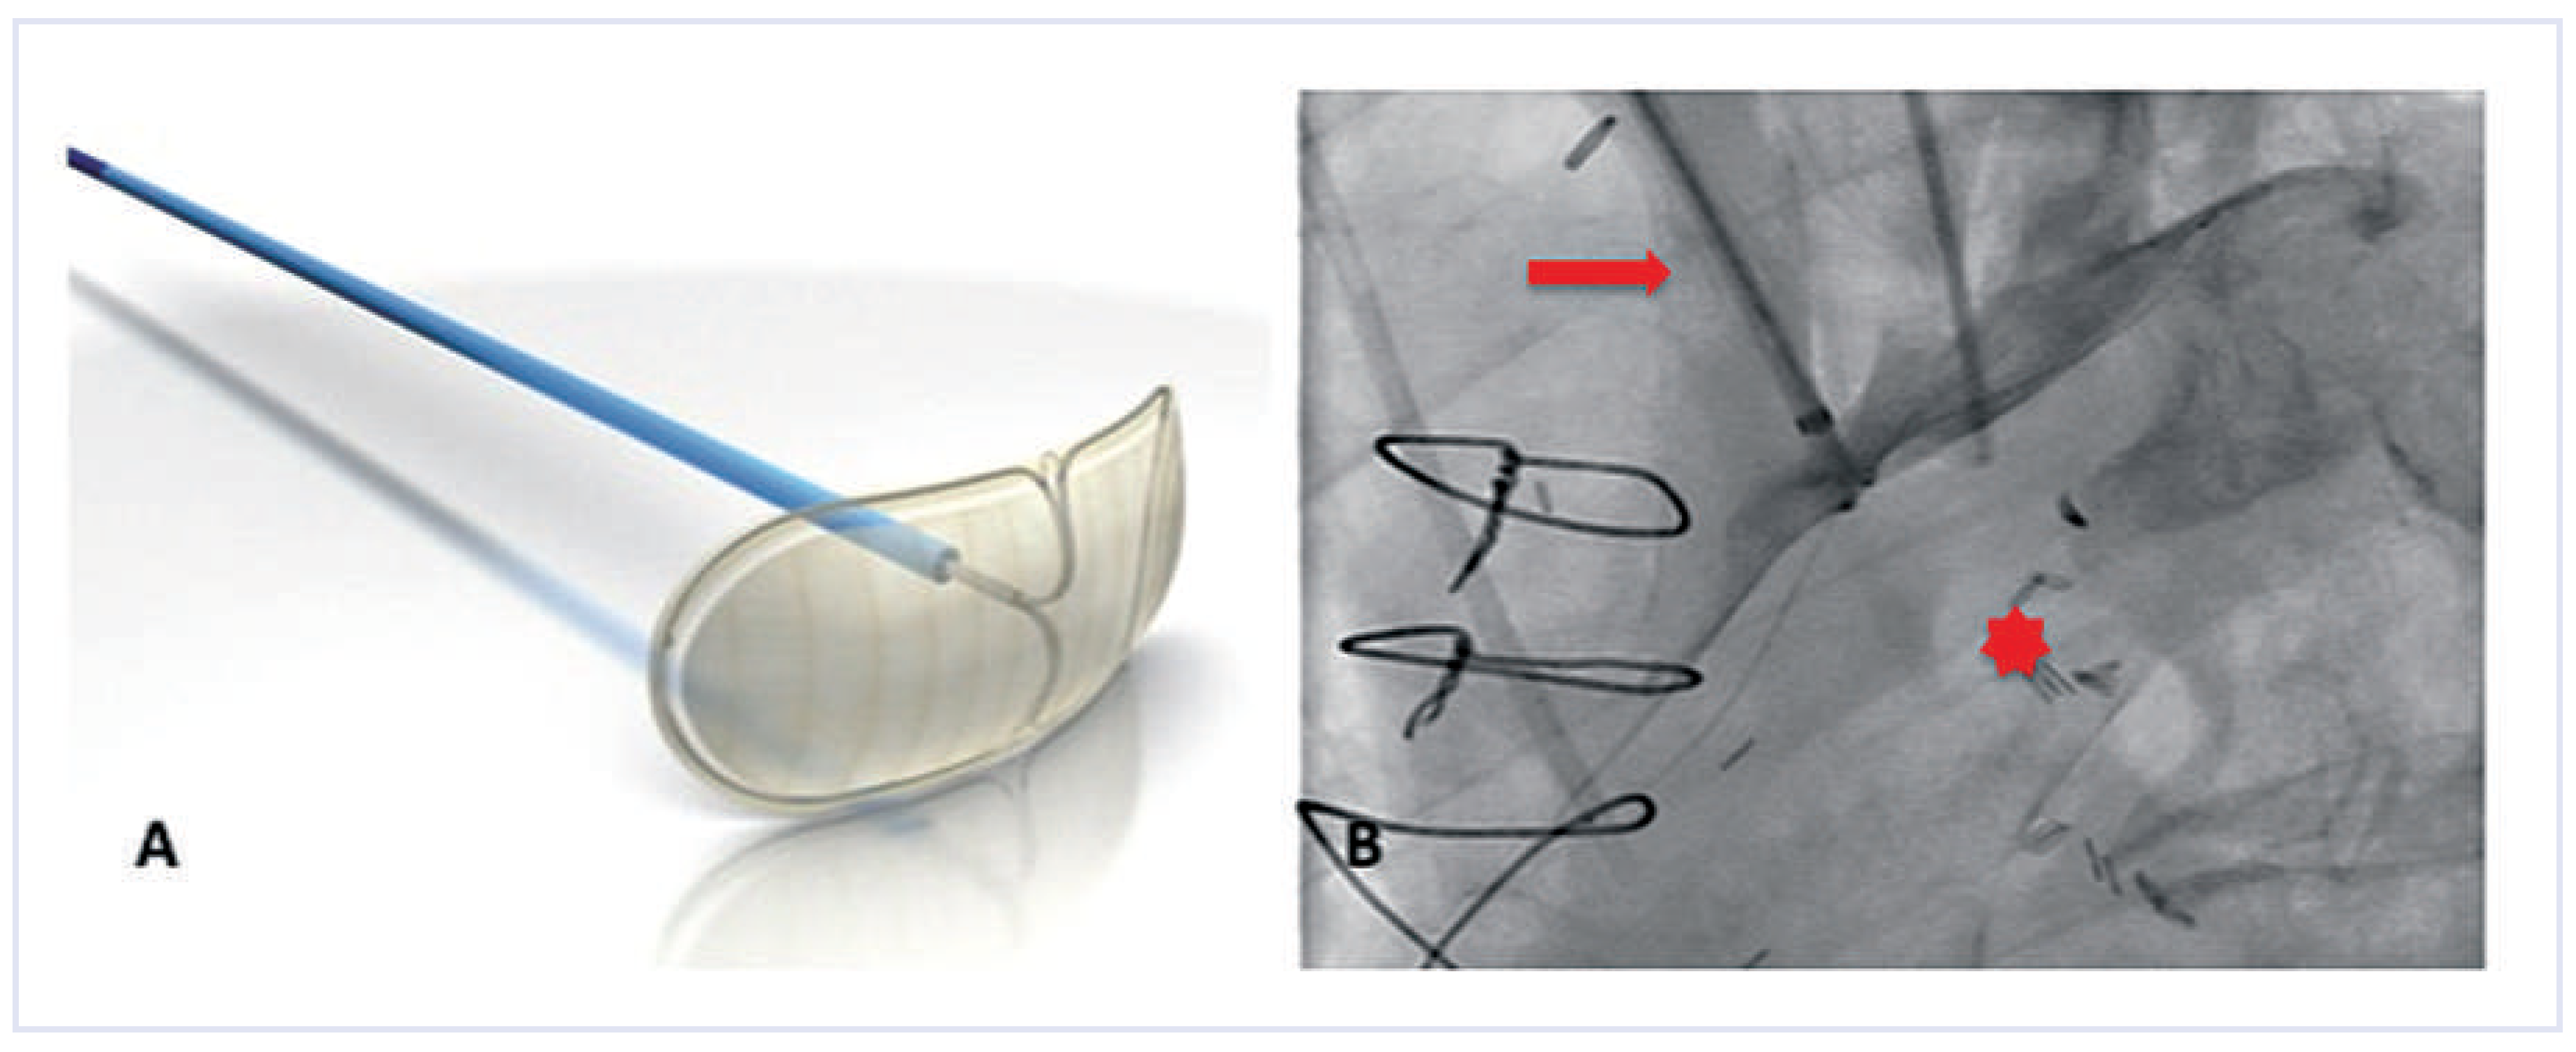

Embol-X

The Embol-X intra-aortic filtration system (Edwards Lifesciences Ltd., Irvine, CA, USA) is a filter device designed for cardiac surgery procedures and was recently used for the first time in a transaortic transcatheter valve implantation [18]. In surgical procedures, the device is deployed in the ascending aorta before release of the cross-clamp. It is introduced through a side port of the aortic cardiopulmonary bypass cannula. The device comes in five sizes accommodating various aortic diameters. The filter consists of a semi-permeable polyester mesh, allowing blood circulation through the filter, while capturing emboli with diameters >120 µm (Figure 7). In a randomised trial on >1200 surgical patients mostly atheromatous emboli were captured by the device in >95% of patients [19]. It was demonstrated that the use of the device led to a significantly lower combined endpoint (neurologic, renal, myocardial, gastrointestinal, peripheral vascular complications and death) in subgroups of patients with a low body mass index, low ejection fraction or previous history of cerebrovascular disease. This difference was mainly driven by a reduction in renal insufficiency.

Etienne et al. [18] successfully utilised the device in transaortic TAVI. An upper mini-sternotomy was performed and under direct visualisation of the ascending aorta, access for the transapical Ascendra delivery system (Edwards Lifesciences Ltd, Irvine, CA, USA) was gained. Distal to the first access site, the aorta was punctured again in order to introduce a 14 French sheath over which the Embol-X device was deployed in the ascending aorta. Although transaortic access is currently not broadly used, it is the only TAVI-access route allowing for concomitant use of this cerebral protection device.

Figure 7. Embol-X: The device consists of the delivery system and a basket to be deployed in the aorta. (Courtesy of Edwards Lifesciences Ltd., Irvine, CA, USA.).